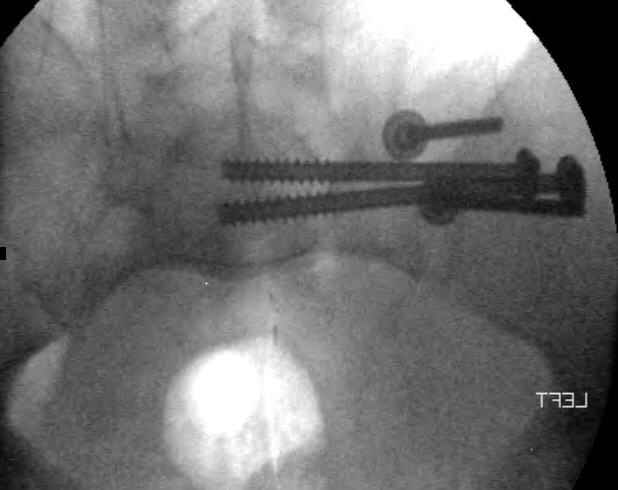

On post trauma day 5 the pt was taken to OR for ORIF of his iliac wing fracture and SI dislocation. The swelling/3rd spacing of fluid in the area of symphysis was profound, but quite acceptable posteriorly.

Patient was prone for procedure, as I thought too difficult to fix the wing in lateral position. Of course the repair of wing was easy, but reduction of SI very demanding. The Floro images document the residual lack of reduction. That was the closest I could get it using 6mm joystick in wing, and clamp on sacrum and clamp through notch. The fixation was (initially) rigid. Anterior ex fix with supra-acetabular pins was placed due to condition of soft tissues, massive "beer-belly" overhanging the crest.